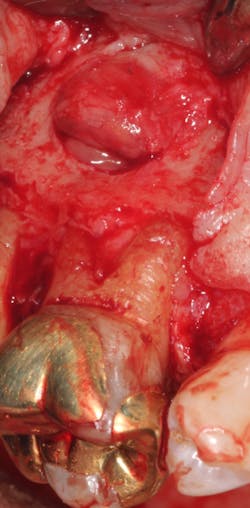

A split- to full-thickness intrasulcular incision was made on the facial of teeth Nos. 2 through 4. Upon completion of flap elevation, an intraosseous cyst associated with the distobuccal root of No. 3 was noted perforating the buccal plate and adherent to the overlying flap (figure 2). A sharp dissection separated the cyst from the flap (figure 3), and the cyst—measuring roughly 1.0 x 0.75 x 0.5 cm—was enucleated intact, leaving an intraosseous defect (figures 4a and 4b).